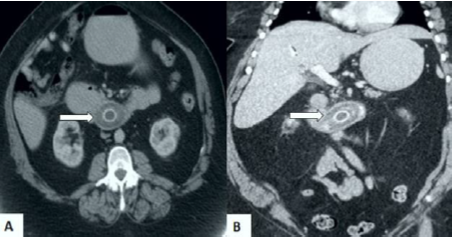

La radiografía de tórax mostró cardiomegalia ligera con ambos campos pulmonares normales y la radiografía de abdomen mostró algunas asas distendidas con niveles de aire y ausencia de neumoperitoneo. La ecografía abdominal mostró que el estómago estaba distendido y lleno de líquido con un túnel de insonación en el duodeno. Las imágenes de tomografía computada revelaron presencia de aire libre en cavidad abdominal, obstrucción de la salida gástrica con presencia de neumobilia, evidencia de colecistitis y una probable fistula colecistoduodenal. Se observó un defecto de llenado con atenuación baja rodeado de material de contraste de alta atenuación en la tercera porción del duodeno, que parecía corresponder a un cálculo biliar (figura 1). Se realizó el diagnóstico de fistula bilioentérica e íleo biliar proximal.

Las imágenes de tomografía computada abdominal con contraste también pueden ser útiles para establecer el diagnóstico del síndrome de Bouveret, ya que puede definir la presencia de la tríada de Rigler. Sin embargo, en 15% - 25% de los casos, el cálculo biliar puede quedar oculto por líquido o bilis circundante en el duodeno (10, 11). En esos casos, la colangiopancreatografía por resonancia magnética es la modalidad de diagnóstico más efectiva, ya que permite delinear el cálculo y detectar los trayectos fistulosos. También es útil en pacientes con alergia al contraste oral. La endoscopia gastrointestinal superior permite identificar la causa exacta de la obstrucción de la salida gástrica y establecer las características macroscópicas del cálculo biliar impactado, pero este es visible solamente en 70% de los casos, probablemente porque la mucosa puede recubrirlo (8, 9, 12).